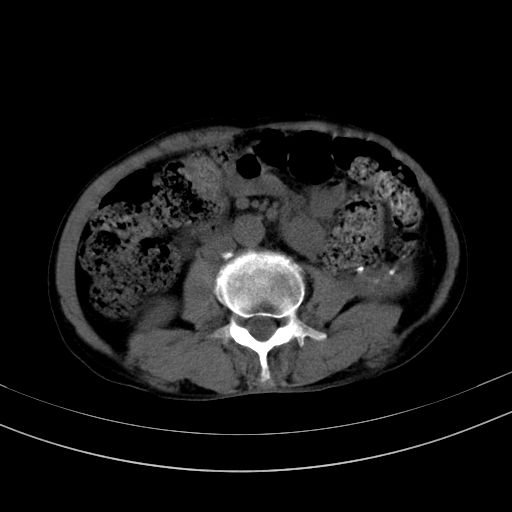

以下是引用37度在2010-1-9 14:37:00的发言:[br]1.双肾囊肿,左肾积水结石,.胆总管轻度扩张;[br]2.病灶在腹膜外,考虑纤维瘤。

以下是引用dyqct在2010-1-9 17:56:00的发言:[br]考虑:1.双肾囊肿,左肾积水结石、旋转不良。[br] 2.右侧腹直肌血肿或纤维瘤。[br]肠道准备不好。做个增强。